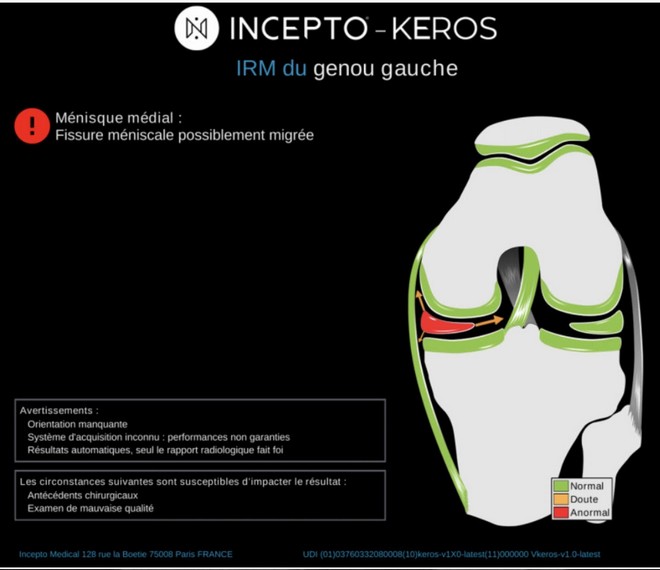

Dans l’univers très encombré de l’intelligence artificielle appliquée à l’imagerie médicale, la start-up française Incepto, créée en 2018, annonce le lancement de son intelligence artificielle d’analyse de l’imagerie du genou par IRM (Imagerie par résonance magnétique). Elle permet la détection et la prise en charge des lésions du genou.

La solution d’Incepto est installée au centre d’imagerie de Soissons. « Nous l’utilisons à la clinique pour l’interprétation de nos IRM du genou. Notre expérience est qu’elle renforce la fiabilité du diagnostic posé par le radiologue » commente le docteur Stephen Binsse, radiologue, de l’AP-HP et du centre d’imagerie Soissons. « Elle permet d’aller droit au but dans son exploration, en identifiant préalablement les lésions potentiellement présentes dans les structures analysées » poursuit-il.

Une première étude clinique en cours de publication montre des gains de sensibilité et de spécificité significatifs sur les différentes structures analysées, le ligament croisé antérieur, le ligament collatéral médial, les ménisques médiaux et latéraux. La solution a été mise au point durant 2 ans avec des médecins radiologues du groupe de radiologie 3R, un groupe suisse de radiologie de proximité qui emploie 30 médecins radiologues, et avec des radiologues experts français.

Cette application est une première pour Incepto qui jusqu’alors mettait à disposition des hôpitaux et centres médicaux des intelligences artificielles médicales via sa plateforme Folio. L’intelligence artificielle développée par Incepto est conçue pour détecter automatiquement les lésions des ligaments, des ménisques et des cartilages. Pour cela, elle emploie 30 algorithmes différents réalisant des tâches telles que la localisation des structures, l’aide au diagnostic, la détection du protocole d’acquisition et des artefacts métalliques, etc. Les algorithmes ont été entraînés sur une base de 25 000 IRMs, multicentrique et multi-machine.

L’intelligence artificielle s’intègre dans le processus de travail du médecin, et doit apporter une réassurance diagnostique au radiologue. Elle permet un gain de temps et facilite la communication avec le patient et les prescripteurs. Les lésions des principales structures anatomiques du genou peuvent être d’origine traumatique ou dégénérative sur les ligaments, les ménisques et les cartilages. Ces lésions sont nombreuses avec 1,5 million d’IRM du genou réalisées chaque année en France.